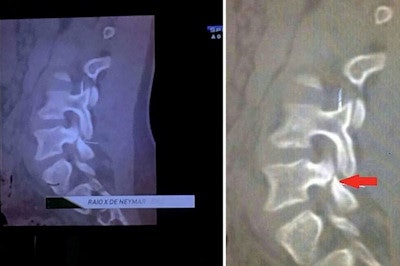

But controversy has been building within the medical community after Brazilian TV posted what it said was an "x-ray image" (actually a CT scan) of Neymar's injured vertebra over the weekend. The image purported to show the damage Neymar suffered in the incident, with some sources claiming that the star could have been paralyzed if he had been hit just slightly higher on the back.

This image has gained much attention after being shown on Brazilian TV, but its authenticity has been questioned.

This image has gained much attention after being shown on Brazilian TV, but its authenticity has been questioned.However, a number of imaging experts have criticized the image, pointing out that it does not show any acute damage to the L3 vertebra; instead, it seems to indicate damage to the L5 vertebra that's more consistent with a chronic condition -- a pathology that Neymar may have been playing with for some time.

Valassina also notes the image posted by Brazilian media does not denote an L3 fracture, but instead spondylolysis of the L5 vertebra: "an interruption of the posterior arch of the vertebra L5 likely ... nontraumatic." In fact, the radiological characteristics of the image seem to suggest an "old disease," Valassina notes.